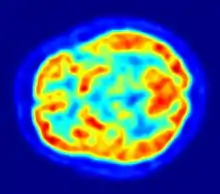

Positron Emission tomography) scanned image of the brain.

- This study [with a PET (for positron emission Tomography) scanner to monitor activity in the brain's visual areas] lends considerable weight to the idea that hypnosis is a real neurological phenomenon," said. But our goal is not just to verify a hypothesis. With hypnosis, we can help people modulate perceptions in ways that are therapeutically helpful.

- David Spiegel, in “Research supports the notion that hypnosis can transform perception.”